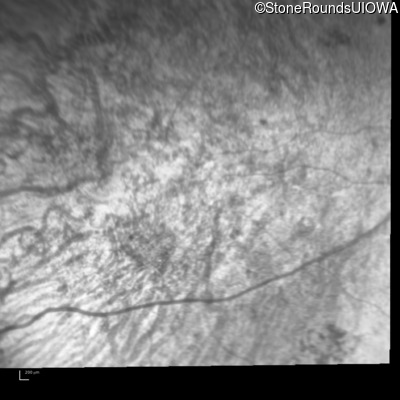

Infrared Fundus Photograph - Right - Hand Motion

Exemplar